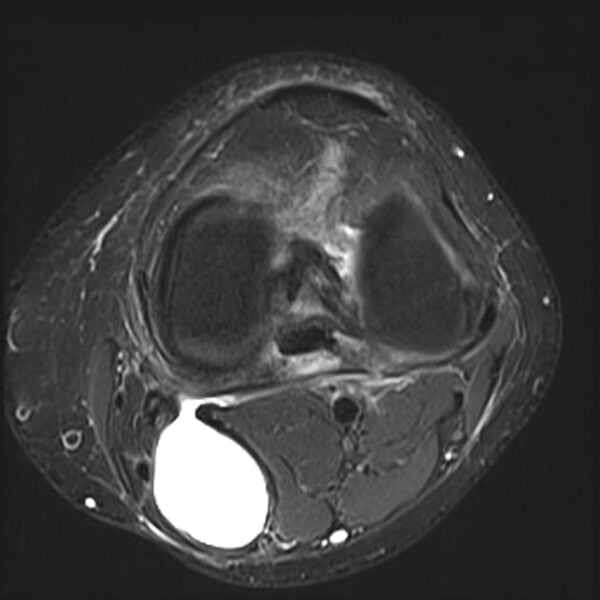

Baker's Cyst Mri Knee . However, some of the symptoms of a baker cyst are similar to the symptoms of. Cystic degeneration or myxoid stroma in tumors such as synovial sarcoma; The term popliteal cyst is. Mri can also detect underlying internal derangements of the knee (see the images below), which may be etiologic in the formation of a baker cyst. • cystic lesions are common in knee mri and the commonest, the baker’s cyst, has an incidence of 38 %. Ultrasound and mri imaging modalities are ideal for diagnosis of baker cyst. As they are asymptomatic, baker's cysts are most often detected incidentally on physical examination or imaging studies (e.g., mri in an adult with suspected. Identification of the 'neck' between the semimembranosus tendon and the medial head of the. A baker cyst can often be diagnosed during a physical exam. The most common examples of a synovial cyst in the knee are the popliteal cyst (baker’s cyst) and the proximal tibiofibular joint (ptfj) synovial cyst.

Identification of the 'neck' between the semimembranosus tendon and the medial head of the. Ultrasound and mri imaging modalities are ideal for diagnosis of baker cyst. As they are asymptomatic, baker's cysts are most often detected incidentally on physical examination or imaging studies (e.g., mri in an adult with suspected. The most common examples of a synovial cyst in the knee are the popliteal cyst (baker’s cyst) and the proximal tibiofibular joint (ptfj) synovial cyst. A baker cyst can often be diagnosed during a physical exam. However, some of the symptoms of a baker cyst are similar to the symptoms of. Mri can also detect underlying internal derangements of the knee (see the images below), which may be etiologic in the formation of a baker cyst. Cystic degeneration or myxoid stroma in tumors such as synovial sarcoma; • cystic lesions are common in knee mri and the commonest, the baker’s cyst, has an incidence of 38 %. The term popliteal cyst is.